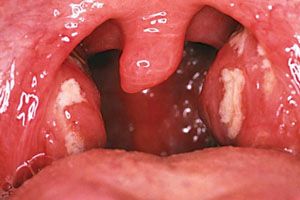

Виникаючі реакції в цих органах, можна умовно розділити на первинні (уражаються тільки гланди) і вторинні (запалення активно розвивається в горлі, ротової порожнини, носових пазухах). Найбільш поширеними недугами є хронічний тонзиліт, гостре запалення (ангіна, гіпертрофія і аденоїди).

- Гланди збільшені, на них присутні червоні бляшки овальної форми,

Основними ознаками є біль в горлі, що не дозволяє нормально ковтати, приймати їжу і розмовляти. На гландах з'являється частковий або суцільний гнійний наліт, збільшуються лімфовузли під нижньою щелепою, турбує неприємний запах з ротової порожнини. Гланди червоніють, запалюються, набрякають. Але є і інші види симптоматики, що характеризують початковий розвиток захворювання ломота в суглобах, жар, утруднення мови. Симптоми схожі на ангіну. але методи лікування в більшості випадків різні.